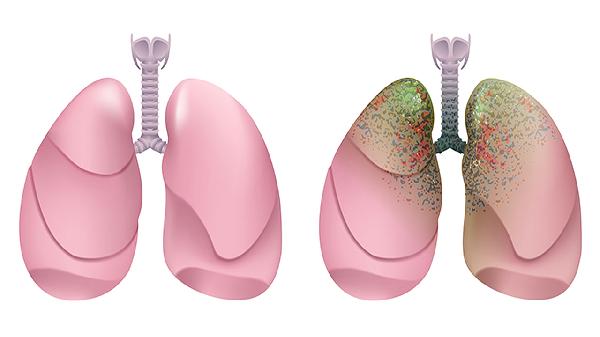

2、手术切除不彻底是甲癌复发的主要原因之一。甲状腺癌手术需彻底切除肿瘤及周围可能受侵的组织,若残留癌细胞,可能导致复发。手术方式选择也影响复发率,全甲状腺切除术较部分切除术复发风险更低。对于淋巴结转移的患者,需进行淋巴结清扫以降低复发概率。

4、术后未规范治疗可能增加复发风险。术后需根据病情进行碘-131治疗,以清除残留的甲状腺组织和癌细胞。患者需长期服用甲状腺激素替代药物,抑制促甲状腺激素分泌,降低复发风险。定期随访和影像学检查可早期发现复发迹象,及时干预。

5、复发后的治疗需根据具体情况制定方案。局部复发可选择再次手术切除,若无法手术,可考虑放疗或碘-131治疗。远处转移患者可采用靶向治疗或化疗,如索拉非尼、仑伐替尼等药物。治疗期间需密切监测甲状腺功能,调整药物剂量,确保治疗效果。